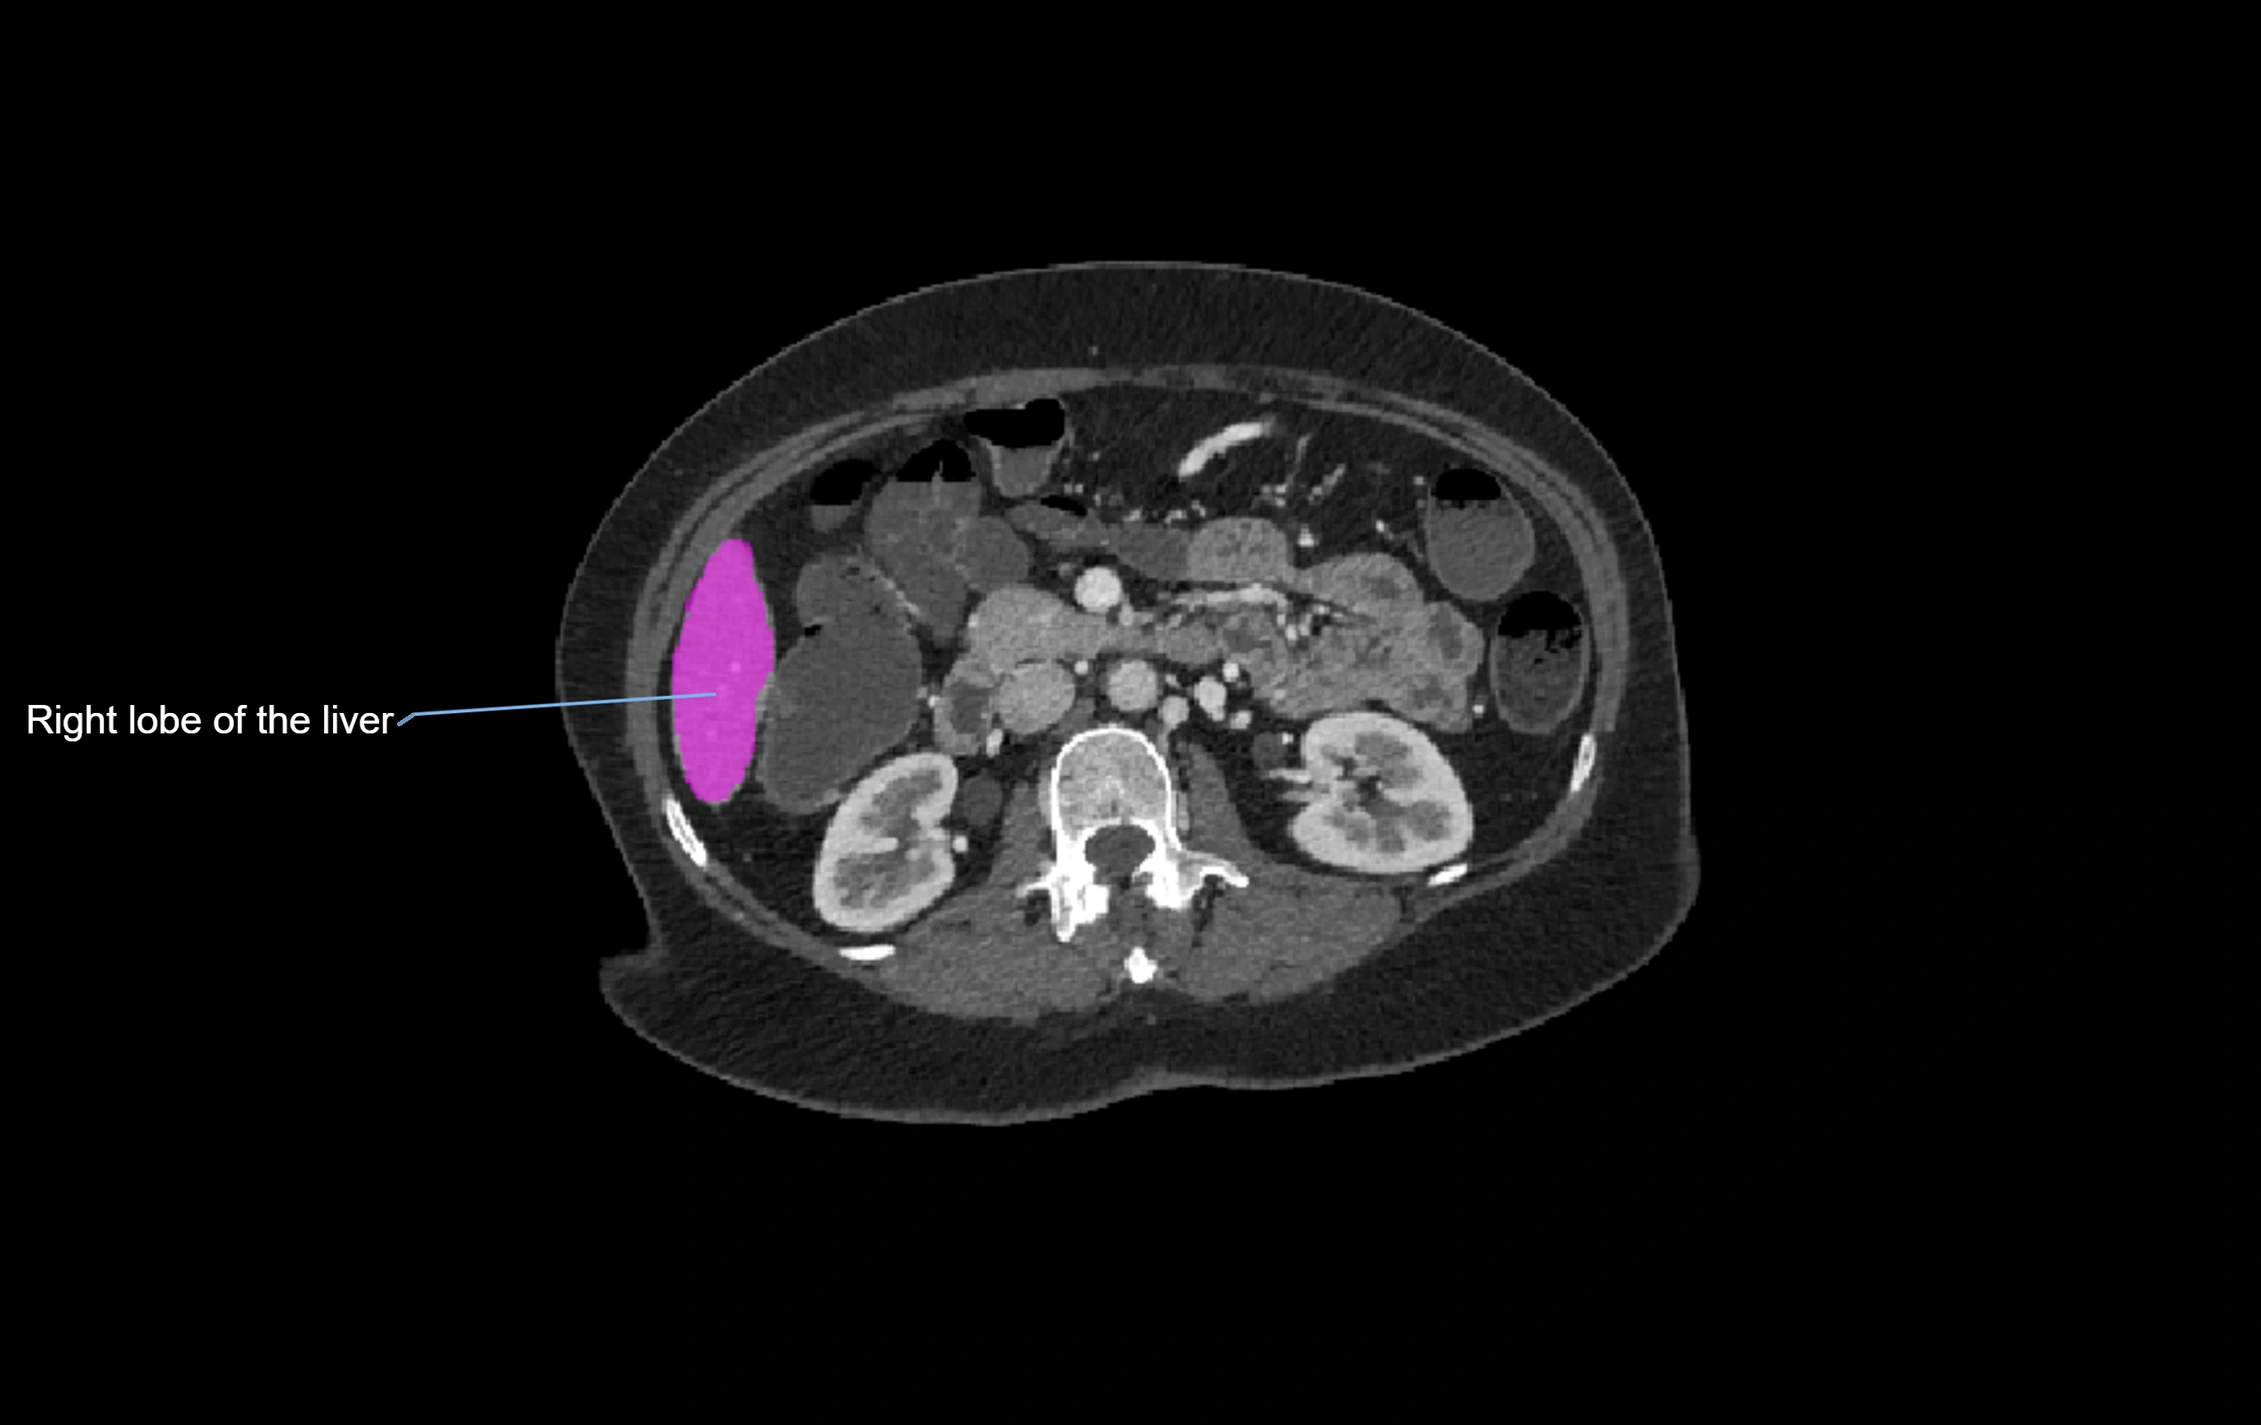

CT Image

image